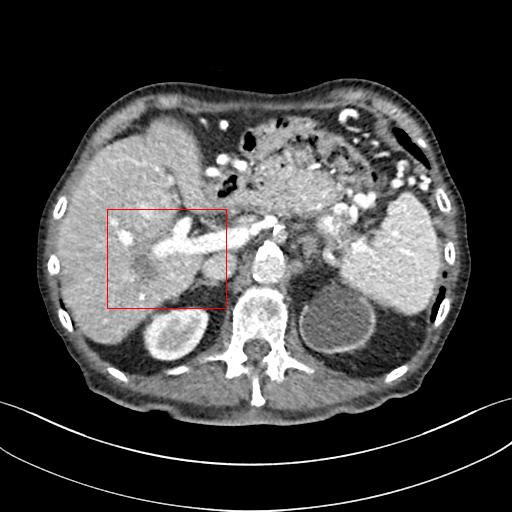

Figure 4: Zoomed version of the ROI taken from the images of Figure 3. In the zoomed version missing boundary pixel is clearly visible in the output of M1.

This section systemically investigates the efficacy of every module proposed in this study. We considered three different networks; first, baseline model(M1), where the inverting block is replaced with dense block, and trained using minimizing mean square distance between two noisy observations(i.e. fsubscript𝑓\mathcal{L}_{f}). Next, two independent baseline model(one for forward mapping, one for reverse mapping) is jointly trained using a linear combination fsubscript𝑓\mathcal{L}_{f}, and rsubscript𝑟\mathcal{L}_{r}, similar to cycle consistent network paradigm. The forward mapping network is used for testing. We refer this model as M2. In both M1, and M2, we increased the depth of the network to make the representation power of these networks comparable with inverting network. Finally, the proposed method, referred as M3. Table 2 depicts the objective evaluation of the three networks using the D1 dataset. Both M2 and M3 use reverse mapping to regularize the network; the influence of the same in the denoising performance is evident from Table 2. Adding cycle consistency loss has improved the performance of the same baseline model significantly. The inverting network performed considerably better than the network M2. It improves PSNR by 0.23dB. As discussed in the above section, in case cycle consistency loss, an additional network is trained, but that does not always guarantee invertibility, whereas inverting network architecture inherently possesses reversibility, which acts as a strong regularizer. In Figure 3 we have shown denoising performance of different networks visually. To demonstrate the requirement of regularization, we first extract the boundary line of the various organ from the NDCT image and superimpose the boundary line on the output of different networks. As shown in Figure 3, many pixels around the boundary line of M1 network output are missing. Using the reverse mapping, the issue of the end-organ missing pixel is successfully overcome in M2 and M3. The granular pattern is also less present in the M3 than M2. The zoomed version of a ROI taken from the images of Figure 3 is given in Figure 4 for better perception. In Figure 5 we give an example of the performance of the invertible network in reverse mapping. Here, the predicted LDCT image is produced by using the predicted clean image of the forward mapping as the input for reverse mapping. As shown, the predicted noisy pattern is similar to the original noise pattern. The same streaking artifacts are present in both the noise pattern; also, the noise variance is different in the various spatial region depending on the signal intensity of the original CT image. It validates that the loss of information in reverse mapping is minimal. Due to the invertible network’s structural advantage, the network also preserves every information present in the input image in the forward mapping.